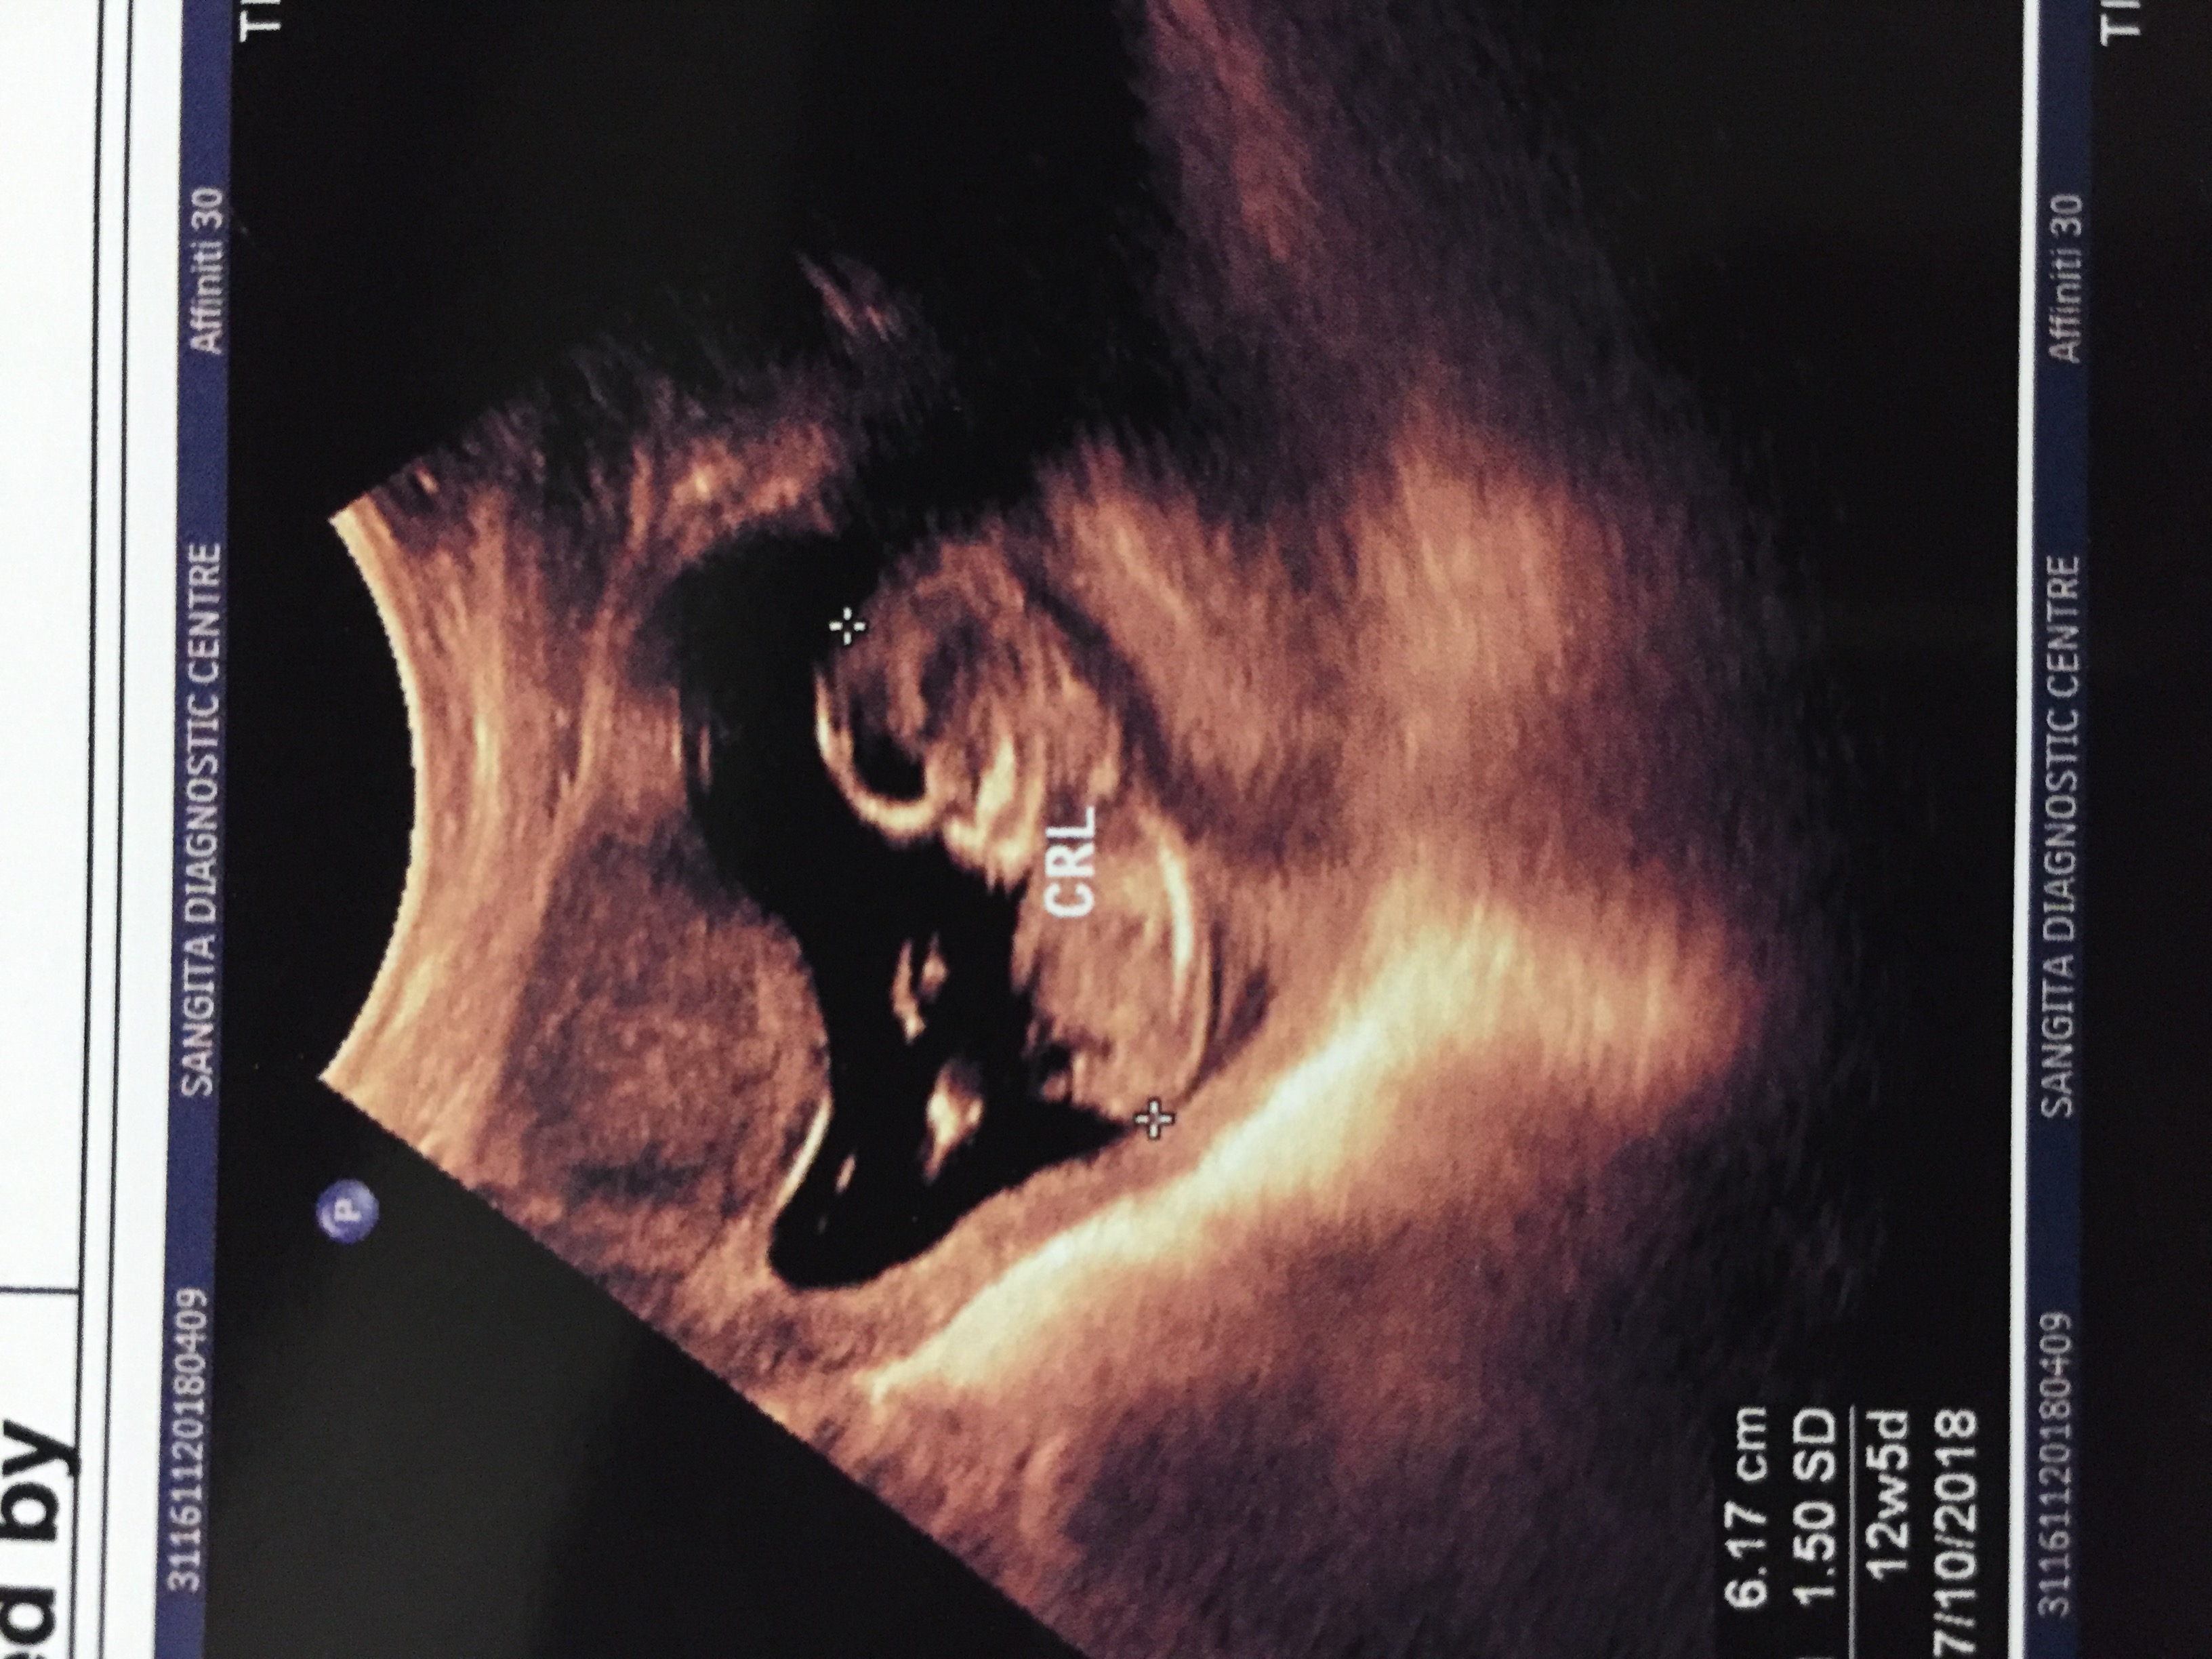

Guessing boy